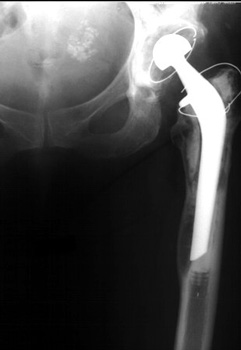

LOOSENING

No prior studies available. Abnormally widened interfaces about femoral component at Gruen zones 1, 6, and 7. Osteolysis at Gruen zone 5 with marked thinning of femoral cortex placing patient at risk for pathologic fracture.

Cement fracture Gruen zone 6 close up next slide

CEMENT FRAGMENTATION

May occur with shift of femoral component.

Transverse fractures of cement near distal femoral stem seen in up to 1.5% of THR, associated with mild subsidence. If less than 4mm, usually not associated with failure. (Weber and Charnley)

CEMENT FRACTURE